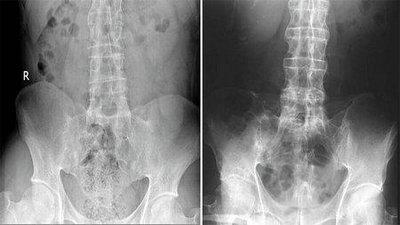

(图:脊柱治疗前后对比图)

第一个疗程结束后,赵先生非常满意,他表示臀部和膝关节的疼痛感明显减轻,全身轻松。

第二个疗程结束后,关节疼痛消失,行走正常;由于赵先生的强直性脊柱炎属于早期,治疗过程比较短,第三个疗程基本是在进行巩固治疗。

三个疗程都结束后,2015年4月2日,赵先生来院复查,蒙兴文主任安排他采用我院较新全力引进技术HD-热层析检测技术检查,经检查,赵先生骶髂脊柱关节炎性病变症状,疼痛表现已消失,身体各项检查也已达到临床治疗标准。